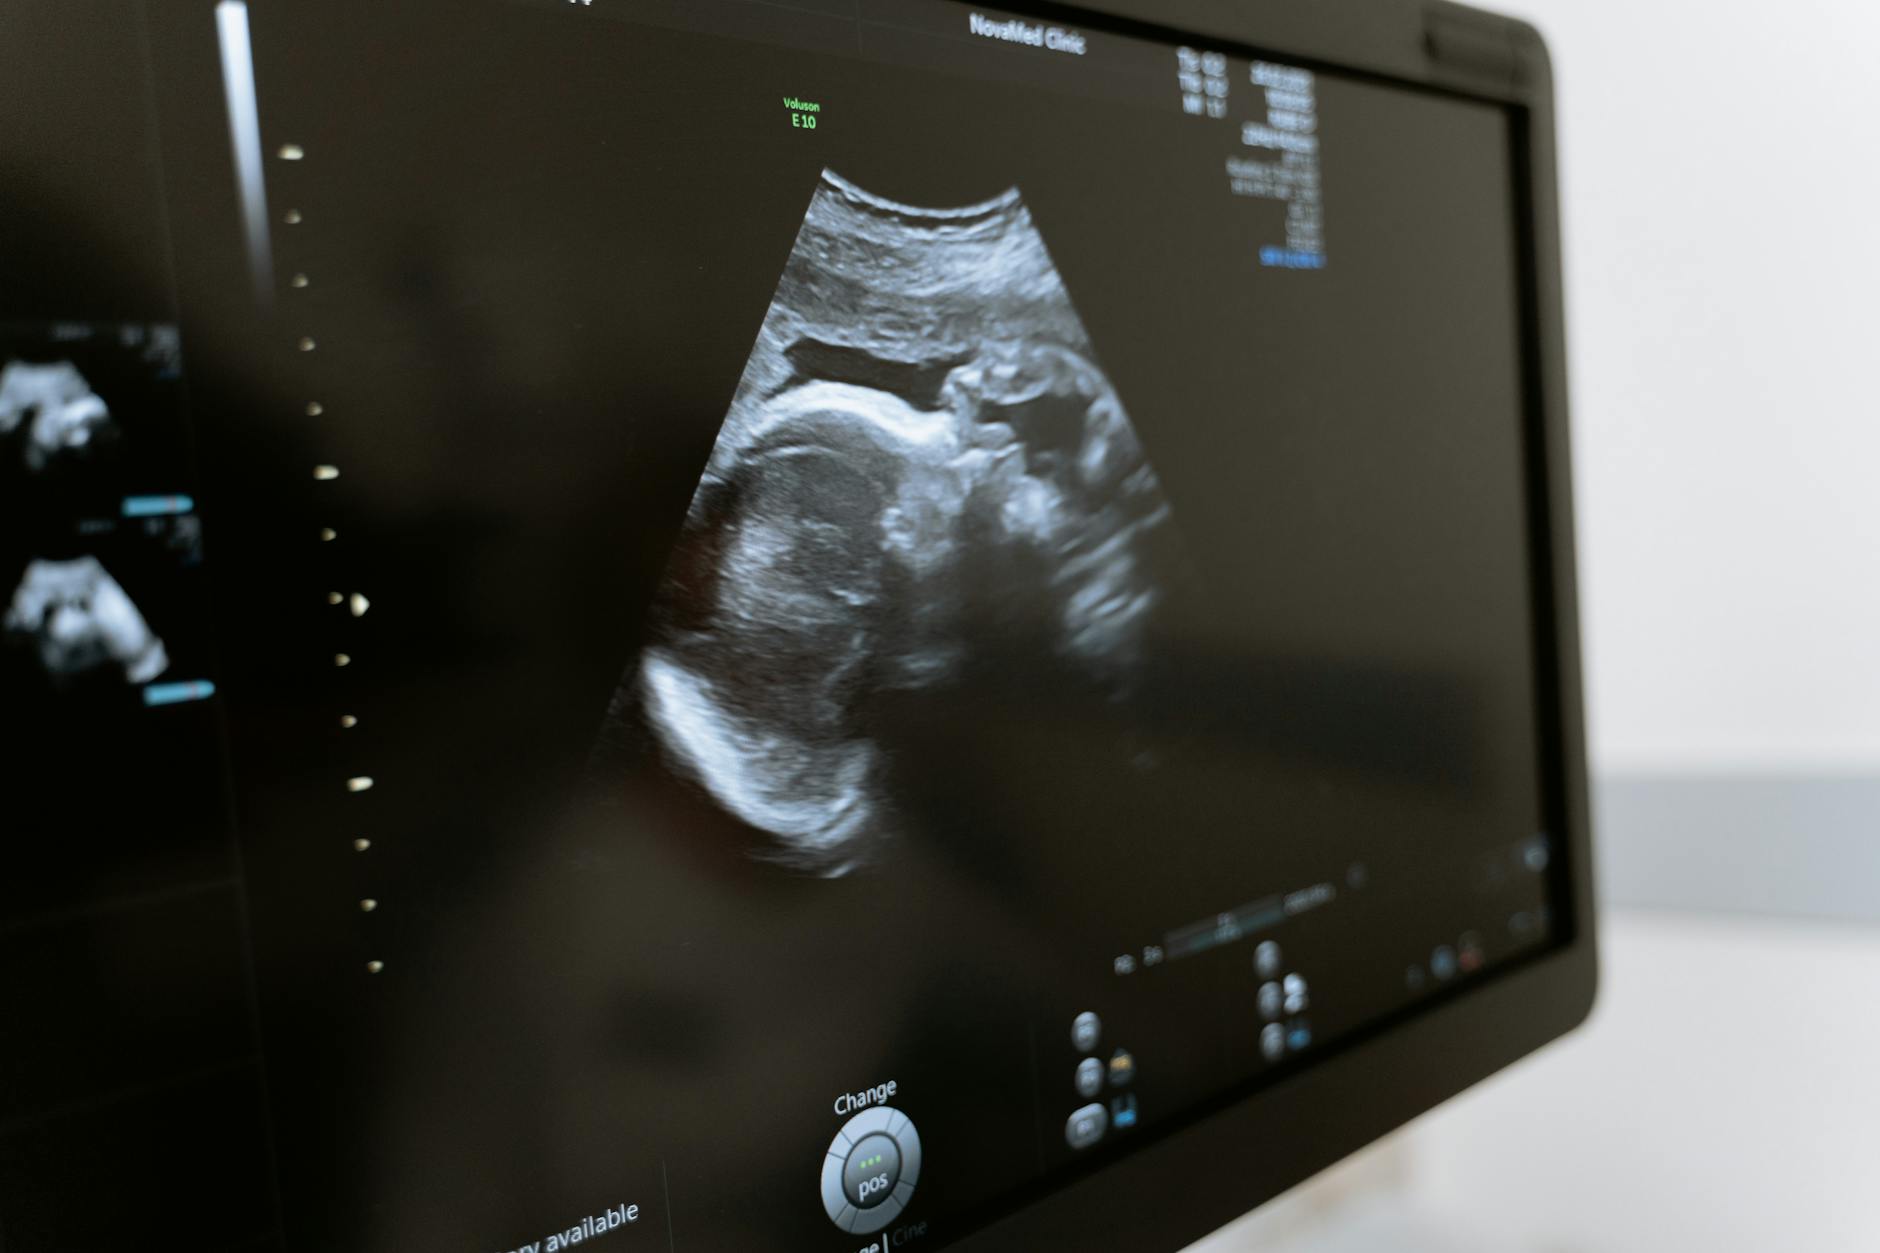

Diagnóstico y seguimiento del foco ecogénico

El diagnóstico se realiza mediante ecografía durante el embarazo, generalmente en el segundo trimestre. Este hallazgo suele ser incidental y no requiere pruebas adicionales a menos que se detecten otras anomalías que puedan sugerir un mayor riesgo de problemas cromosómicos.